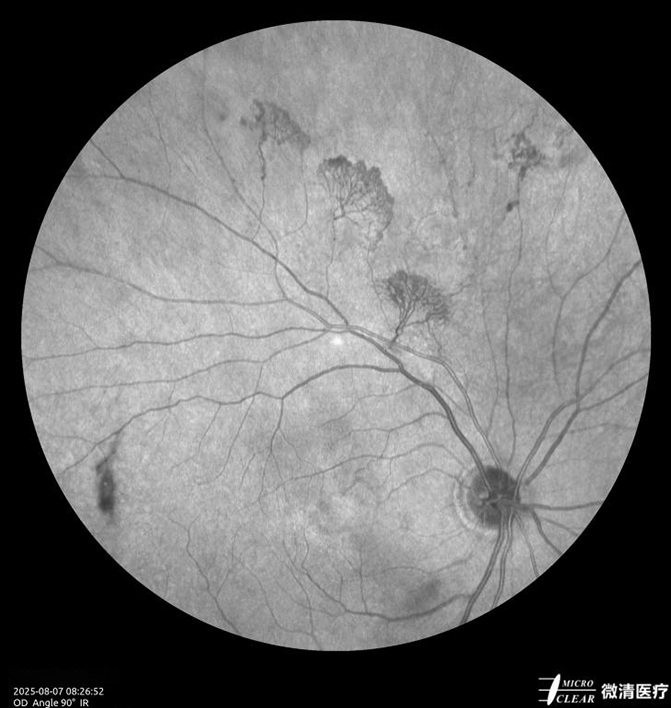

8.视网膜分支静脉阻塞/廊坊市广阳区眼科医院

1758873743787423.png

1758873750670754.png

1758873757205088.png

1758873762860454.png

1758873770751246.png

(1) 一、患者基本信息:女性,69岁

(2) 二、主诉:右眼视物不清10天。